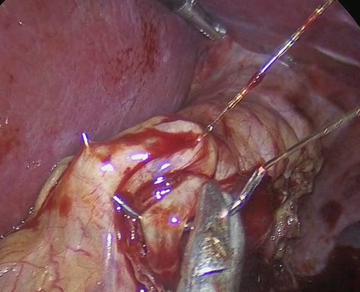

The SG is then performed by dividing the gastroepiploic omentum from the greater curvature with an ultrasonic scalpel (Sonicision TM Medtronic) starting 6cm from the pyloric vein to the angle of His, until the left crura of the hiatus was observed. The gastro-splenic and gastro-phrenic ligaments are also divided. The fat pad that covers the His angle is excised with the same instrument. A 36Fr bougie is passed to the stomach to construct the gastric tube using five or six cartridges of the Endo GIA 60 tristaple (CovidienTM) to divide the greater curvature. The proximal gastric plication is then performed to create an internal antireflux valve in the upper 3cm on the lateral side of the gastric tube by using a grasper to invaginate 2cm of the gastric wall of the stomach with sero-muscular stitches of a running suture of 2-0, 45cm spiral Monocryl (Stratafix Ethicon ®), and then continue the suture to reinforce the rest of the staple line (Figure 1-3). This invagination reduces the gastric bulb that is frequently observed at the proximal staple line and serves to decrease the gastric lumen at this point; serving as an internal anti-reflux valve.

Figure 2 Grasper invaginating 2cm of the upper stapled side of the stomach tube wall to create the antireflux valve with proximal gastric plication.